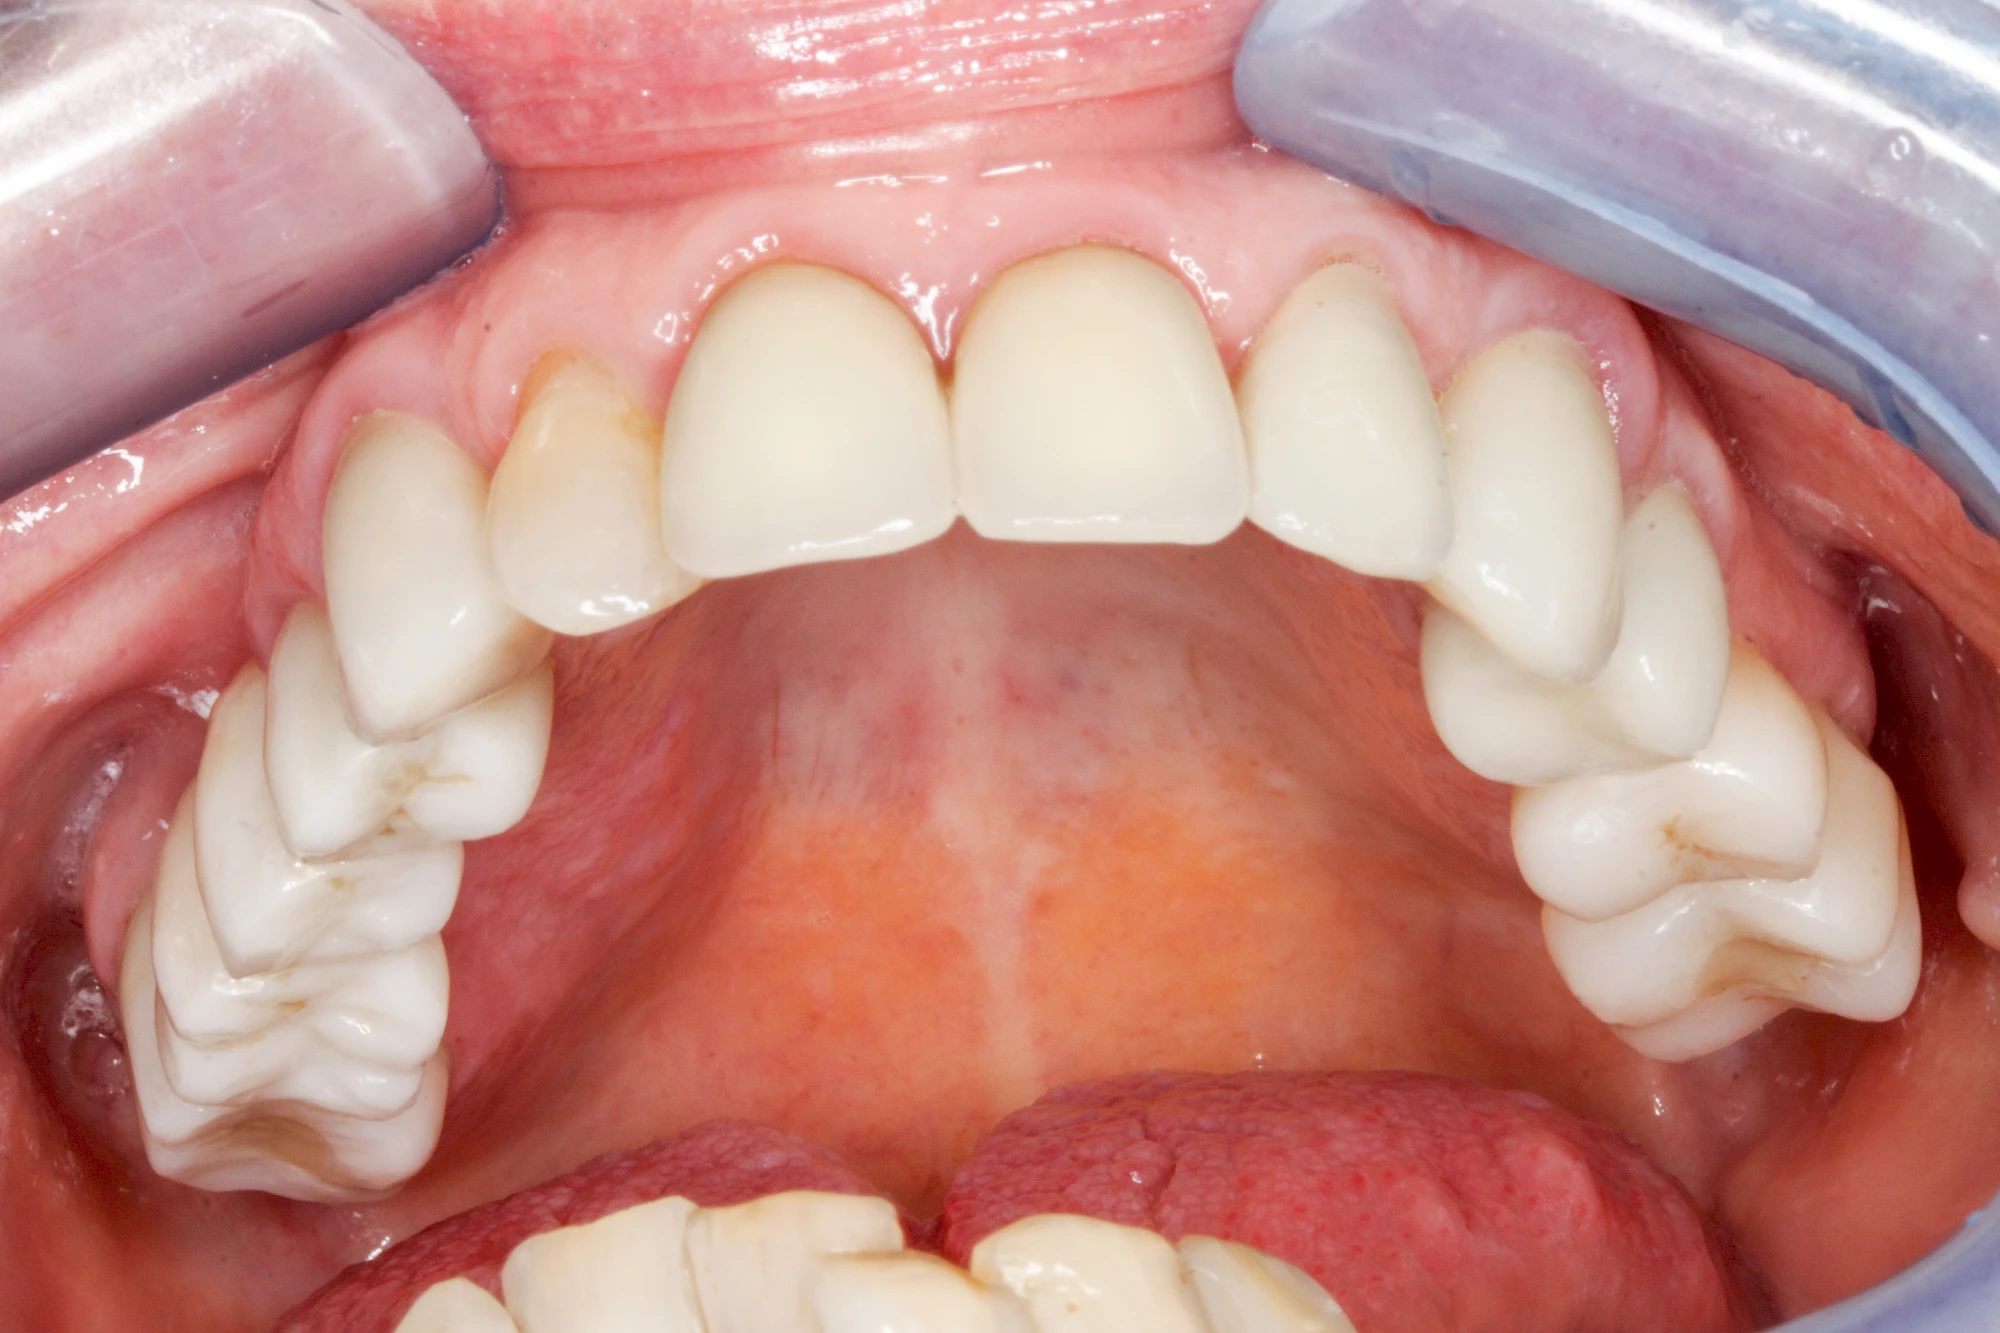

Diese Vermehrung von Bindegewebe in einem frei gewordenen Raum ist eine Sonderform der Anpassungsreaktion menschlicher Zellen und wird als Vakatwucherung bezeichnet.

Früher wurden im Unterkiefer mitunter Brücken zum Ersatz fehlender Zähne als sogenannte "Schwebebrücken" gestaltet. Die Idee dabei war, dass man die Brücke insgesamt besser reinigen kann. Allerdings war das für die Patienten mitunter irritierend für die Zunge und vor allem beim Essen gewöhnungsbedürftig. Teilweise haben sich hier reaktiv Vakatwucherungen der Kieferkammschleimhaut gebildet und den Raum unter der Brücke wieder verschlossen.